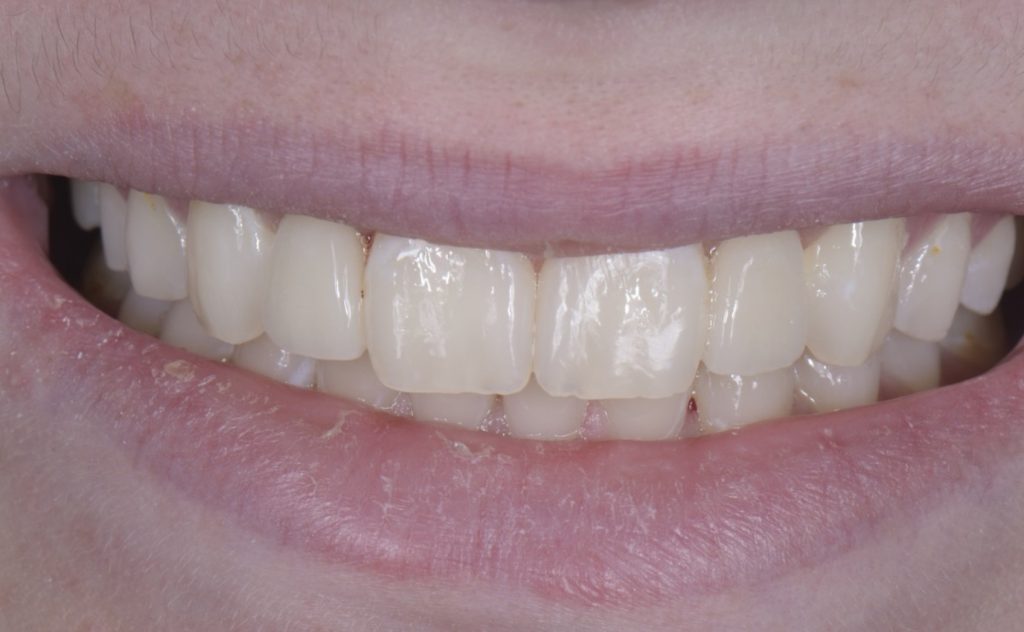

Solution #1: Canine Substitution for Missing Lateral Incisors

Canine substitution is the least invasive option and a popular alternative, but it often poses esthetic and functional challenges that need to be considered and cleared (Fig. 1). From an esthetic standpoint, the canine’s shape and shade must be considered. From a contour standpoint, the width of the canine should be evaluated because they are generally larger than lateral incisors.

However, the most critical aspect to manage is the CEJ width because it cannot be narrowed. The wider the tooth at the CEJ, the more difficult it is to make a canine look like a lateral incisor. Moreover, canines typically present with a very distinctive root eminence, and if it is particularly accentuated, it could become yet another esthetic challenge — one commensurate with the patient’s lip mobility.

There is no major esthetic concern for patients where a low lip line conceals the gingival outline. Still, if there is high lip mobility and the gingival outline is not concealed, such an eminence could represent an unacceptable esthetic problem.

From a shade standpoint, canines usually are the teeth with the most saturated chroma in the maxillary arch, which often creates an esthetic challenge where this oversaturation is evident.

Consequently, considering these aspects, the ideal clinical scenario for canine substitution would be in patients with smaller shaped canines that are not oversaturated with chroma and in patients who display low lip mobility.